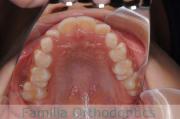

No.19V-044

- 主な症状:

- 上顎前突

- 年齢:

- 13歳

- 性別:

- 女性

- 抜歯部位

- 上:

- 44

- 下:

- 8558

- 主な使用装置:

- FEA

- 治療にかかった費用:

- 85万円

出っ歯を治したいということで小学生の時に来院されました。中学生になるまで経過観察をして、診断、上下左右から小臼歯を抜歯してマルチブラケット法にて治療を行いました。2年強、30回程度の通院が必要でした。

口元の突出感も大きく改善しています。

- ≫治療前

上下とも前歯の叢生(でこぼこ、凹凸、ガタガタ)がありましたので、保定をしっかりやらないと後戻りのリスクが出てきます。